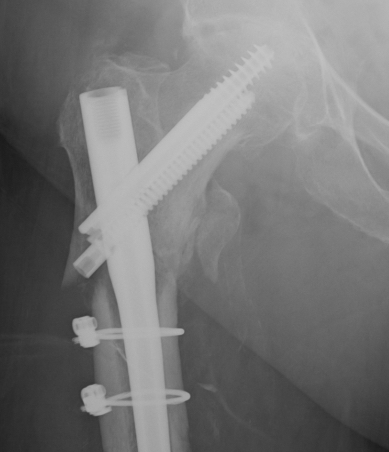

- clamp assisted reduction of displaced subtrochanteric fractures

- all fractures within 5 degrees of anatomical in two planes

- 43/44 fracture united

Kim et al Eur J Trauma Emerg Surg 2022

- systematic review of 14 studies and 1700 patients

- faster union and better outcome scores with cerclage wiring

- no difference in non union rates

Percutaneous

- ball tipped spikes to reduce deformity

- steinman pins to proximal and distal fragment to reduce deformity

- blocking screws laterally and posteriorly in proximal fragment

Open

1. Short transverse fracture

- clamps on proximal and distal fragments and hold reduced

- consider unicortical small plate to hold reduction

- consider blocking screws

2. Longer spiral fractures

- clamping and cerclage wiring with longer spiral fractures